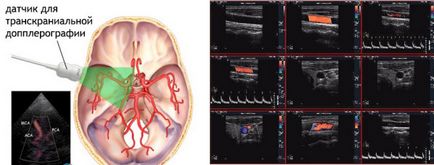

- Studiul transcraniana se aplică numai pentru a supraveghea starea navelor ale capului.

Studiul transcraniana și metoda duplex

- Studiul a creierului state, în special în cazul în care medicul suspecteaza dezvoltarea unei boli asociate cu vasele de sange (infarct miocardic, accident vascular cerebral, etc.). Aceeași tehnică contribuie la identificarea spasmului și ocluzia vaselor de sânge, provocând o funcționare defectuoasă a creierului;